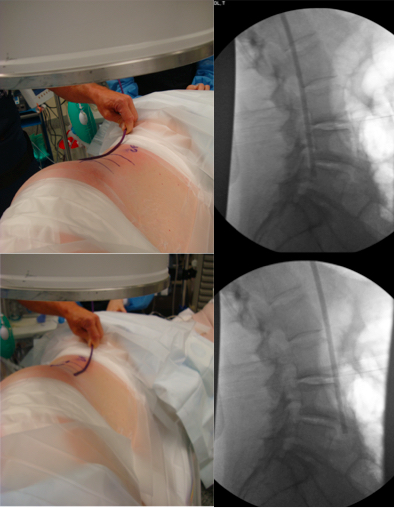

Descargas

3. Pawar A, Hughes A, Girardi F, Sama A, Lebl D, Cammisa F. Lateral lumbar interbody fusion. Asian Spine J 2015;9(6):978-83. doi: 10.4184/asj.2015.9.6.978

6. Berjano P, Gautschi OP, Schils F, Tessitore E. Extreme lateral interbody fusion (XLIF®): how I do it. Acta Neurochir (Wien) 2015;157(3):547-51. doi: 10.1007/s00701-014-2248-9